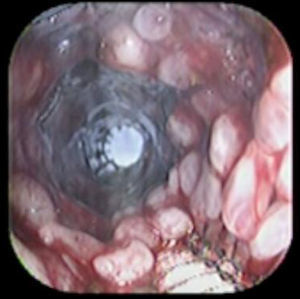

Case reportA 41-year-old man underwent elective laparoscopic Heller myotomy for achalasia; during the procedure a perforation of the esophageal wall was observed, and primary closure of the defect was attempted. The patient started with PO on day three, but he complained of chest pain and fever. Immediately CT scan with oral contrast was performed. A free leakage at esophago-gastric junction was observed. A 15cm PSEMS (Ultraflex esophageal NG covered (120mm) stent, Boston Scientific, Natick, MA) was placed across the defect, leading to the distal 1.5cm non cover into the stomach and the proximal 1.5cm non cover at 30cm from incisor (Fig. 1). A control CT scan with oral contrast showed good position of the stent, without evidence of leakage. The patient's clinical status improved and began to swallow normally, but showed numerous episodes of reflux despite PPI use. We leave the PSEMS for 26 days beside the reflux symptoms. During the endoscopic procedure to remove the stent the presence of tissue embedding along the covered portion of the PSEMS was noted (Fig. 2). The stent was pulled out with an alligator forceps with out major complications and the cover of the PSEMS was seen to be totally destroyed (Fig. 3).